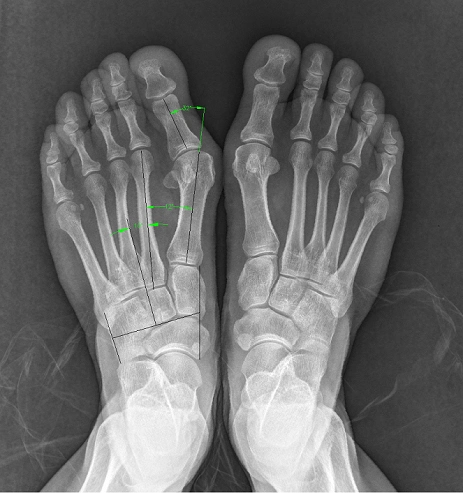

对于重度拇外翻(拇外翻角大于40°,第1,2跖骨间夹角大于20°),除常规